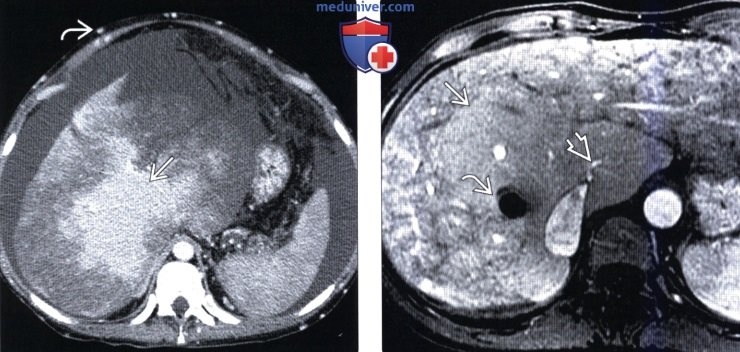

Как мы ставим диагноз? 🔍

Здесь на помощь приходит современная диагностика. «Золотым стандартом» является УЗИ органов брюшной полости с допплерографией. Этот метод позволяет увидеть и сам тромб в просвете вены, и отсутствие кровотока в ней, и увеличенную печень, и асцит.

Для уточнения могут назначить КТ или МРТ-ангиографию – чтобы получить детальное трехмерное изображение сосудов.